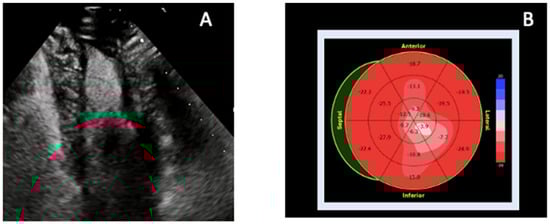

Left ventricular non-compaction (LVNC) is one of the most challenging differential diagnoses when evaluating apparent apical obliteration [59,60,61]. As emphasized in the 2023 ESC Cardiomyopathy Guidelines [62], LVNC is now considered a morphological trait rather than a distinct cardiomyopathy, since excessive trabeculation may occur physiologically (e.g., pregnancy, athletic remodeling) or across multiple pathological phenotypes, including dilated, hypertrophic, and arrhythmogenic cardiomyopathies [59,63]. Although traditionally attributed to incomplete embryogenic compaction between weeks 5–8 [59,64], contemporary evidence demonstrates that hypertrabeculation may also be acquired or adaptive and may regress when the inciting stimulus resolves [63]. Genetic studies have shown how pathogenic variants in MYH7, MYBPC3, TNNT2, and ACTC1—classically associated with HCM or DCM—are common in LVNC, with marked familial heterogeneity, incomplete penetrance, and variable expressivity [59,65,66]. TTE is the first-line modality for identifying LVNC, but diagnostic criteria vary widely. Early definitions include the Chin ratio (X/Y ≤ 0.5) [67], Jenni’s end-systolic NC/C ratio >2 with color Doppler evidence of perfused recesses [64] and Stöllberger’s requirement of ≥3 prominent trabeculations with intertrabecular spaces perfused from the LV cavity [68]. However, all criteria show modest reproducibility and tend to overdiagnose LVNC, especially in patients with ventricular dilation or hypertrophy [59]. In addition, apical foreshortening, poor acoustic windows, and anatomical complexity may hinder differentiation between true non-compaction and obliteration from thrombus, fibrosis, or hypertrophy [69,70]. Contrast TTE improves endocardial border delineation and allows visualization of recess perfusion: microbubble opacification within deep trabecular spaces supports LVNC, whereas absent perfusion favors thrombus or fibrotic obliteration [71]. Functional techniques, including strain imaging and tissue Doppler, demonstrate abnormal apical rotation or paradoxical twist mechanics, reflecting disrupted fiber architecture and supporting the diagnosis [71]. CMR has transformed LVNC evaluation. Petersen’s diastolic NC/C ratio ≥2.3 yields high sensitivity and specificity [72]. These CMR criteria have been validated in large cohorts and are now integrated into contemporary diagnostic algorithms for LVNC [62,72,73]. while Jacquier’s trabeculated mass >20% of LV mass and Grothoff’s threshold of ≥25% non-compacted mass—with basal involvement—predict pathological LVNC and adverse outcomes [65,73]. Tissue characterization further refines differential diagnosis: isolated LVNC typically exhibits minimal or absent fibrosis, whereas ApHCM demonstrates localized thickening with patchy LGE [74]. CMR feature-tracking strain may reveal reduced apical rotation or mechanical dispersion [63]. CMR-detected hallmarks of LVNC, including excessive trabeculation, deep recesses, and thin compacted layer are shown in Figure 3. Cardiac CT provides high-resolution delineation of apical contours and may clarify recess morphology, compacted/non-compacted transitions, or confounding variants when echocardiography and CMR are inconclusive [74]. Correct identification of LVNC in the context of apical obliteration is essential due to its association with arrhythmias, thromboembolism, and systolic dysfunction [75,76]. Conditions mimicking LVNC include ApHCM, apical LVT, and restrictive or hypertensive cardiomyopathies. In ApHCM, wall thickness exceeds 15 mm with preserved compacted myocardium and characteristic LGE [60]. Thrombus appears as a non-enhancing mass on LGE-CMR or contrast TTE [77]. Restrictive and hypertensive cardiomyopathies may cause apparent apical obliteration but lack deep perfused recesses [65]. Some patients show overlapping LVNC–HCM–ApHCM features, supporting a morpho-functional continuum [66].

Figure 3. CMR features of left ventricular non-compaction. CMR provides superior delineation of trabecular anatomy, enabling confident distinction between true LVNC and other causes of apparent apical obliteration such as thrombus, ApHCM, and EMF. (A) Four-chamber SSFP cine image demonstrates a markedly trabeculated apex with deep intertrabecular recesses and a thin compacted myocardial layer. (B) Two-chamber SSFP cine view confirms prominent apical trabeculation and recess communication with the ventricular cavity, fulfilling morphological criteria for LVNC. The combination of excessive trabeculation, deep perfused recesses, and reduced compacted layer thickness differentiates LVNC from ApHCM (which shows compacted hypertrophy), EMF (subendocardial fibrosis with true apical cavity loss), and apical thrombus (avascular mass without recess perfusion). Original images from our institution (single patient).